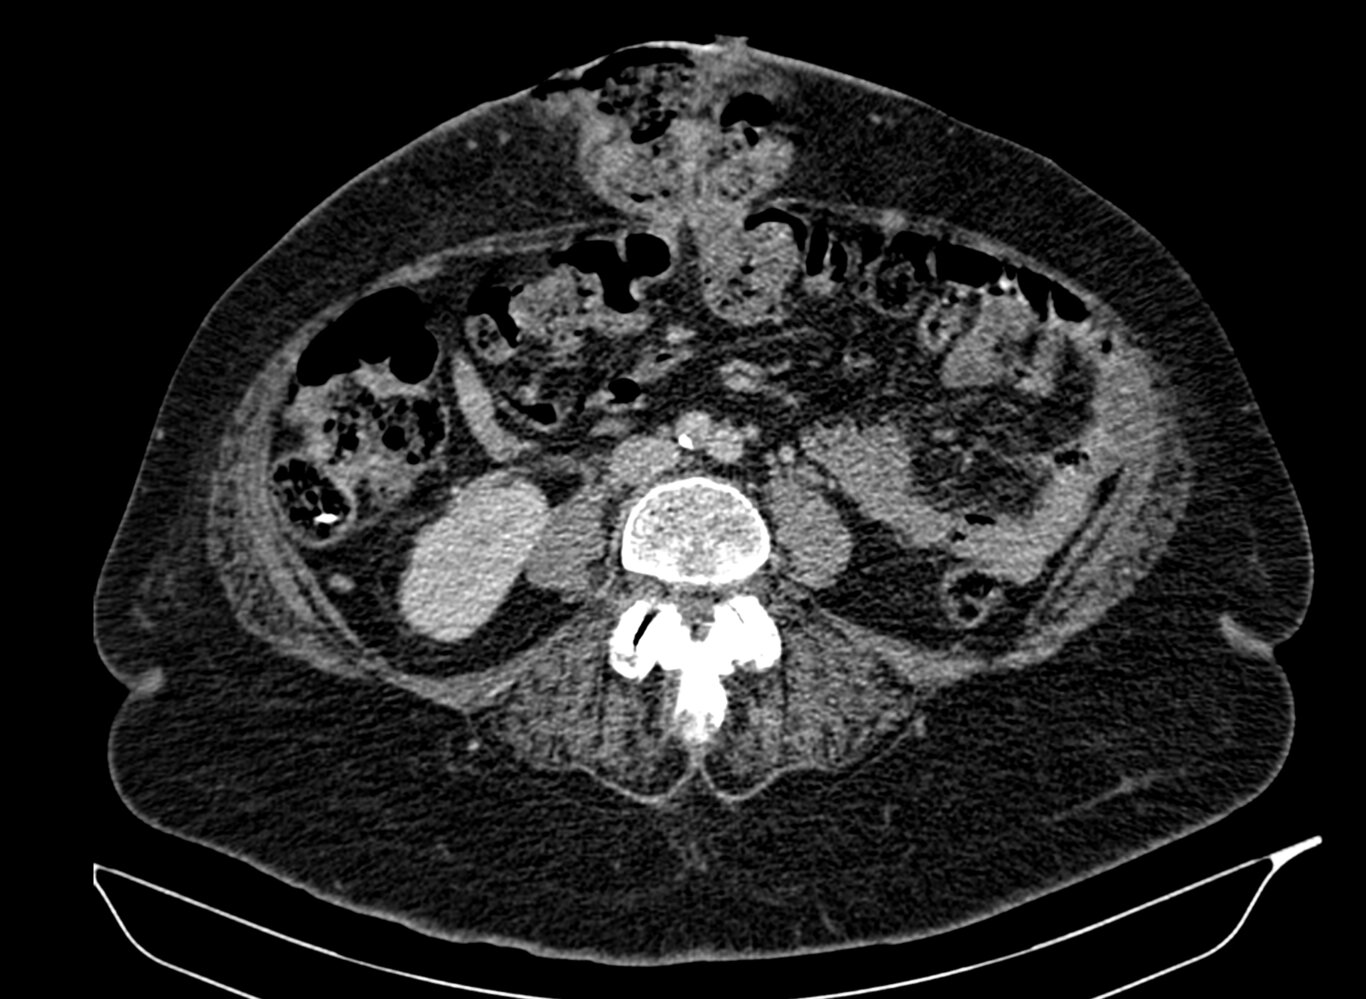

• CT abdomen

• Sensitive imaging study for suspected bowel obstruction or strangulation [10]

• Typically performed with both IV and PO contrast (unless contraindicated because of obstruction)

• Can facilitate planning for complex hernia repair [23]

• Abdominal x-ray: may be used to rapidly evaluate for bowel obstruction and perforation

Findings

• Direct visualization and quantification of the fascial defect(s)

• Presence of viscera in the hernial sac

• Strangulated hernia: signs of visceral ischemia [25]

• Obstructed hernia: radiological signs of mechanical bowel obstruction